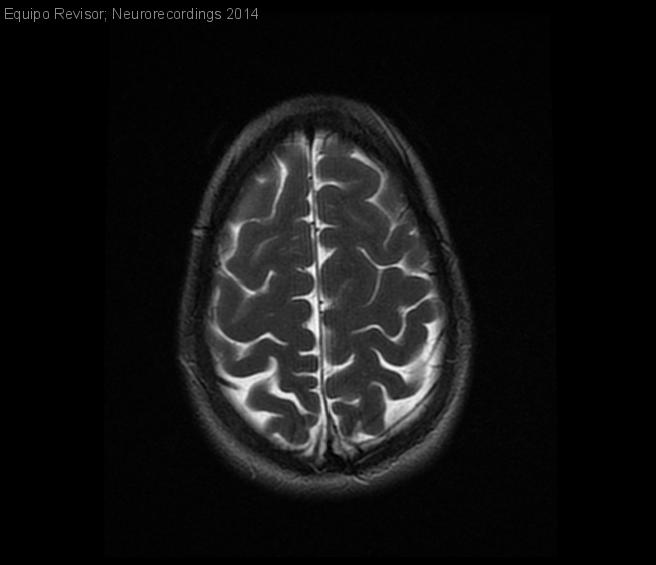

Mujer | 32 años

Diagnóstico final: Displasia cortical focal probable

Desde la adolescencia ha presentado cefaleas tipo opresiva frontotemporal que con los movimientos empeora. Sonofobia, fotofobia, ocasional sensación nauseosa y vomitó en una ocasión. En 2010, refiere que d se ha incrementado la intensidad y...